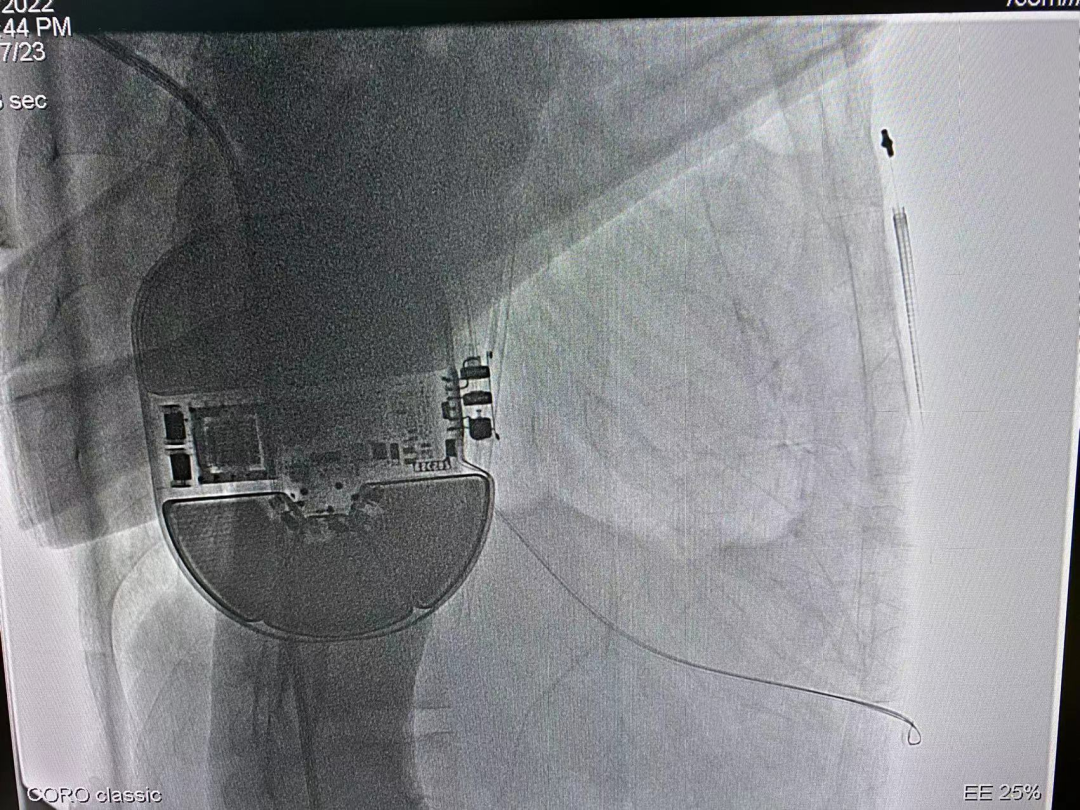

2022年6月17日,由中山大学附属第五医院心律失常科王欢主任团队独立地为一位年轻的心脏性猝死一级预防的患者成功植入本院首例皮下植入式心律转复除颤器(S-ICD),术程顺利。

接受本次S-ICD植入手术的患者是一名41岁男性,因“尿毒症性心肌病、扩心病待排,心功能III級;频发室性性早搏、短阵室性心动过速;慢性肾脏病CKD5期”,收住入院。经系列辅助检查,该病例特点有:(1)尿毒性心肌病;(2)频发室性早搏,彩超显示全心扩大,LVEF20%,属于1.5级预防;(3)无起搏需求;(4)慢性肾脏病CKD5期,左侧血管造瘘,长期血液透析。

根据术前评估和猝死预防相关的最新指南,该患者属于猝死极高危人群。因患者感染风险高、预期寿命长,且无起搏需求,有对日常生活影响小等诉求,为避免传统经静脉置入ICD可能导致的血管并发症风险及心室除颤电极可能导致的相关并发症及提升患者日常生活质量和满意度,经过与患者及家属充分沟通,王主任为患者选用了目前全球唯一可兼容核磁全身扫描检查的皮下植入式除颤器(S-ICD)。

AP